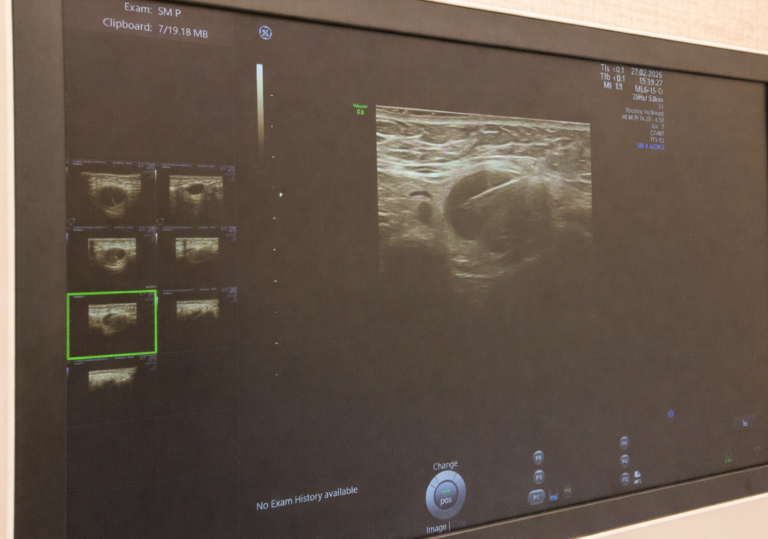

2D ехография на млечни жлези

Работим с най-модерната и прецизна апаратура на GE Healthcare за образна диагностика. В Медицински център „АЯ“ използваме съвременни технологии с фокус върху качеството на образа, прецизната оценка и комфорта на пациента. Центърът разполага с ехографски платформи GE Voluson 8 и GE LOGIQ™ e, както и с интегрирана 3D система Senographe GE Pristina + Serena GEN II.